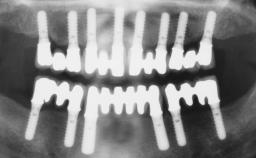

Fixed and removable prosthodontic implant therapy for restoration of the edentulous maxilla is both complex and challenging. Careful assessment and planning is needed in each individual case to explore whether a fixed or a removable solution will be the more suitable to satisfy the patient’s preference for optimal esthetics, phonetics, comfort and function. This Learning Pathway explores the prosthodontically driven treatment planning based on structured assessment, considered diagnosis and practical application in clinical case examples.

• recognize the importance of a prosthodontically driven plan and of planning implant configurations and placement accordingly